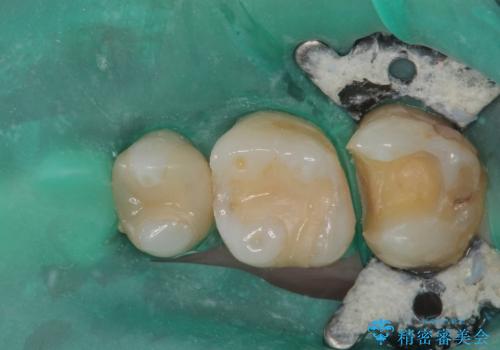

歯と歯茎の間に圧排糸と言われる糸を入れてシリコーン印象材にて精密な型どりをしました。

セラミックインレーの装着時には、唾液の侵入を防ぐために、ラバーダム防湿を行いました。